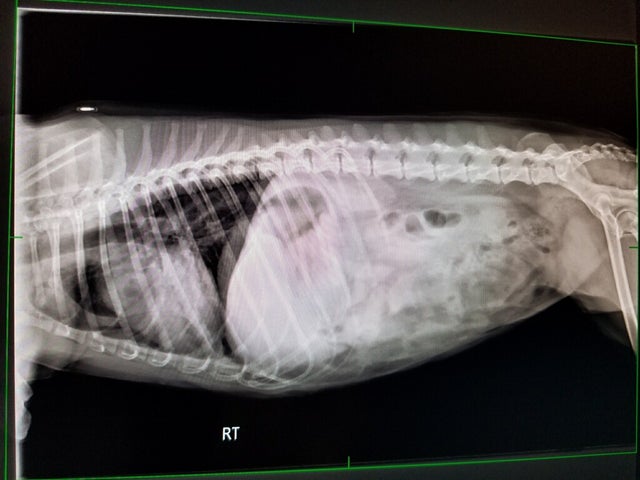

Police say that Sophie was kicked with such force that it collapsed a lung and displaced her heart.